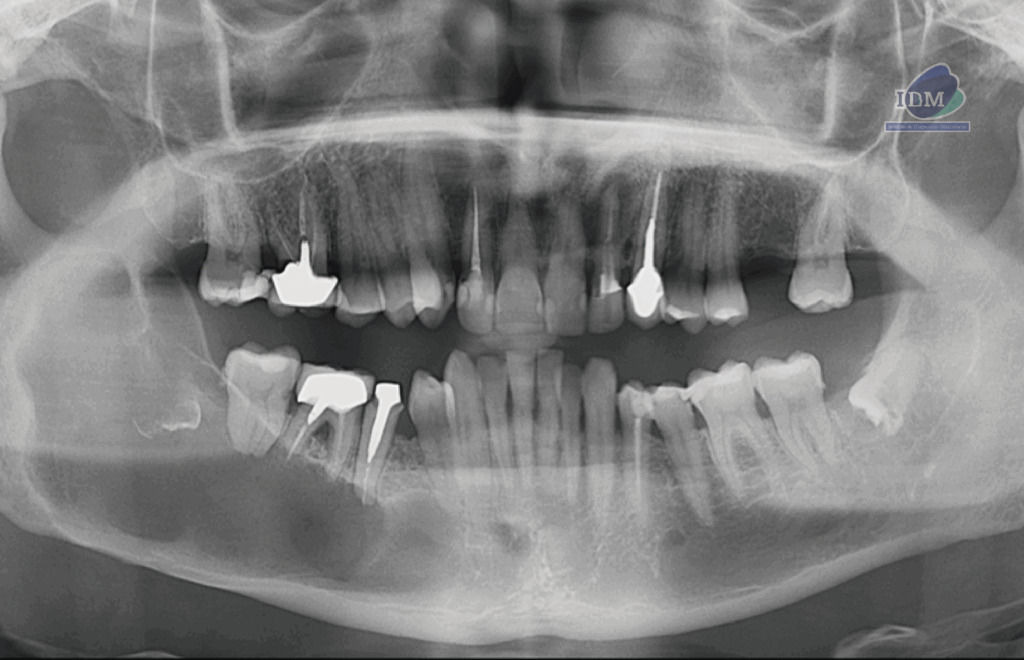

En la radiografía panorámica (Figura 1), se observa una lesión radiolúcida de limites definidos y bordes parcialmente corticalizados ubicado en cuerpo, ángulo y rama mandibular de lado derecho con una extensión desde pieza 44 hasta rama ascendente mandibular y desde la escotadura antegoneal hasta la basal mandibular, ocasionando expansión en el borde anterior de la rama y reabsorción externa en piezas 46 y 47. Además se observa una imagen radiopaca irregular en el interior de la lesión en zona de pieza 48.

Radiografia Panorámica